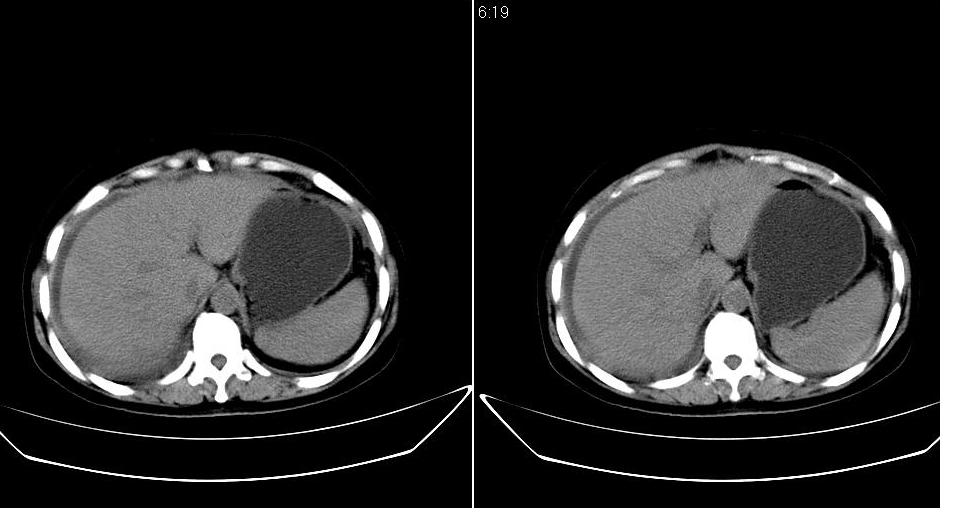

以下是引用zbp537在2009-1-19 14:09:00的发言:[br]从这个平扫图像上看,只能考虑:1、胸腹水。2、脾脏包膜下弧形高密度影,疑出血,建议复查。[br]既然腹水中有恶性细胞,建议行腹部ct增强扫描及胸部扫描。

以下是引用随光逐影在2009-1-19 15:47:00的发言:[br]1)不排除胃癌可能;建议行胃镜检查。2)腹水。3)右侧胸腔积液。

以下是引用jiangjing在2009-1-19 18:21:00的发言:[br]1 网膜污垢征---肿瘤网膜转移.2)腹水。3)右侧胸腔积液